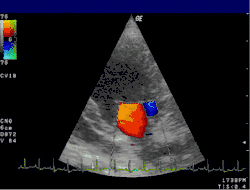

PW mód umožňuje měřit nejen změnu frekvence mezi vysílaným a přijímaným signálem, ale i dobu, za jakou se odražený signál vrátil k sondě. To umožňuje určit nejen rychlost toku, ale i hloubku, ve které došlo k obrazu. Doplerovské měření v PW módu je možné na většině běžně používaných přístrojů, výsledek se zobrazuje jako dvojrozměrný obraz naměřených rychlostí. Výsledky se obvykle kódují barevně (barevně kódovaná doplerovská sonografie) – čím vyšší je v daném bodě rychlost k sondě, tím jasnější odstín červené je zobrazen v odpovídajícím místě na monitoru, a čím je větší rychlost od sondy, tím je zobrazen jasnější odstín modré. Tato volba barev má tu výhodu, že místa s turbulentním prouděním ze zobrazí žlutě. Aby byla umožněna orientace v obraze, obvykle se spojí obraz barevně kódované doplerovské sonografie a anatomický obraz kódovaný do stupňů šedi; výsledný obraz se nazývá duplexní sonogram (též duplexní sono nebo jen duplex).